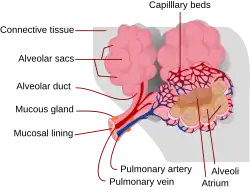

Plicní sklípek (latinsky alveolus, množné číslo alveoli) je dutý útvar v plicích podílející se na struktuře plicních váčků. Představuje základní funkční jednotku plic, ve které dochází k difuzi plynů (oxidu uhličitého z těla a kyslíku do) mezi vzduchem a krví, pomocí kapiláry (vlásečnice) – tedy k vlastnímu dýchání.

Každý plicní sklípek má přibližně 200 mikrometrů v průměru a při nádechu se zvětšuje.[1] Plicních alveol je v každé plíci přibližně 350 milionů a jejich celková plocha se odhaduje na 140 m².[2]

Stěna plicních sklípků je složena především z pneumocytů, které se zde vyskytují ve 2 typech.

- Pneumocyt I. typu (označovaný i jako membranózní pneumocyt) je plochá buňka, která zajišťuje vlastní difuzi plynů.

- Pneumocyt II. typu (granulární pneumocyt) je celkově menší, ale výrazně tlustší buňka, která produkuje plicní surfaktant – látku, která se rozprostře na vnitřním povrchu sklípků a ulehčuje průnik kyslíku z plicních váčků do krve. Při poškození alveoly se asi 1 % pneumocytů II. typu začne dělit, změní svou strukturu a nahrazuje tak odumřelé pneumocyty I. typu.[2]

V plicních sklípcích jsou přítomny ještě alveolární makrofágy, které mohou se vyskytovat jak mezi jednotlivými pneumocyty, tak i volně uvnitř alveol. Zajišťují pohlcování vdechnutých částic a jiných drobných nečistot a jejich transport pryč z plicních váčků. Na některých místech plicních sklípků se vyskytuje i mezibuněčná hmota (extracelulární matrix), která zajišťuje mj. elasticitu plicních sklípků.

Alveokapilární membrána

K plicním sklípkům přisedají zvenku vlásečnice, které přivádějí odkysličenou krev a odvádějí krev obohacenou o kyslík. Tyto vlásečnice tvoří s pneumocyty I. typu a několika málo dalšími podpůrnými vrstvami tzv. alveolokapilární membránu,[3] přes kterou probíhá vlastní přenos plynů ze vzduchu do krve a naopak. Je obvykle jen 100–1500 nanometrů silná.[2]

Jednotlivé plicní sklípky jsou propojeny s okolními sklípky póry o průměru 10–15 µm. Ty slouží k vyrovnání tlaků mezi sklípky a umožňují také cirkulaci vzduchu v případě zneprůchodnění některé průdušinky.[2]